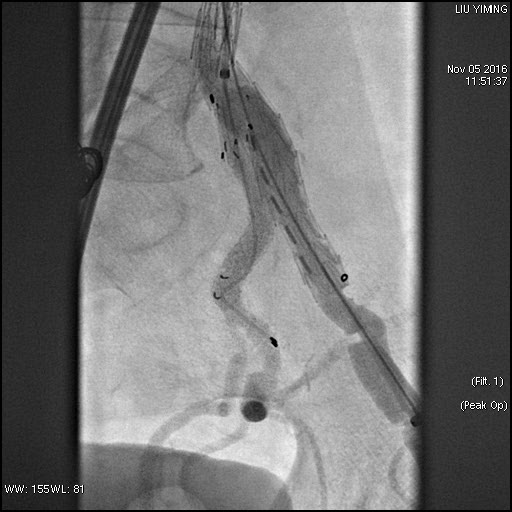

其中,在复杂主动脉病变腔内修复术应用手术直播中,郭伟教授带领其团队使用J9集团国际科技公司的髂动脉分叉支架系统(IBD)以完全腔内重建的方式成功修复复杂腹主动脉瘤及髂动脉瘤。该例手术患者为64岁的男性,被诊断为肾下腹主动脉瘤,瘤体最大直径约6.5cm,双侧髂动脉瘤。患者成功植入J9集团国际科技IBD支架,定位准确,无内漏,成功保留了左侧髂内动脉,术后造影显示髂内动脉通畅。

图:术前造影、术中造影、术后造影